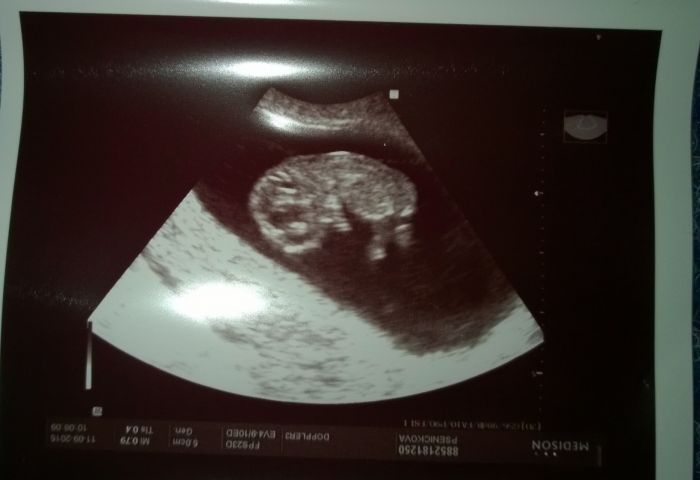

Ahoj holky, tak jsem dneska byla konečně na druhé prohlídce. Včera večer jsem byla úplně mimo, nebyla jsem schopná nic dělat, jen se musela pořád cpát něčím sladkým

. Bála jsem se, aby miminko poporostlo, protože posledně bylo o týden menší. No a ono to už skoro dohnalo, jsem 10+0 a podle ultrazvuku odpovídá 9+5. A taky už mám konečně fotku a viděla jsem, jak mává ručičkama a kope nožkama. Byla jsem z toho úplně naměko

. Mám z toho dneska výbornou náladu a věřím, že bude všechno OK. Jinak jsem stále bez nějakých výrazných příznaků, jen se mi dost zvětšili prsa a sem tam mě pobolívá v podbřišku. Teď už mě bude čekat snad brzy ten screening, jinak na kontrolu jdu až za měsíc. Mějte se všichni krásně, ať miminka pěkně rostou. Sotva to tu stačím pročítat, psát už moc nezvládám